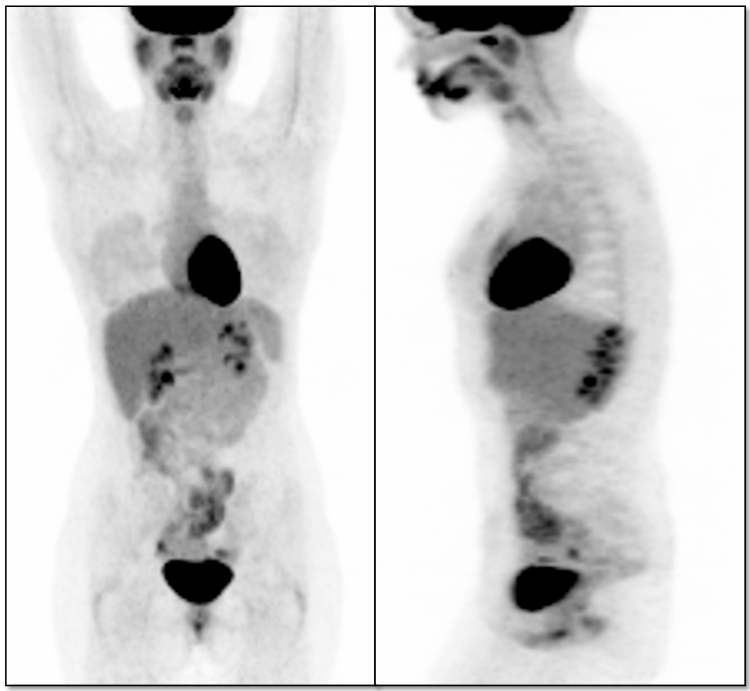

- Whole Body Assessment

- The “You’re Kidding Me!” Effect